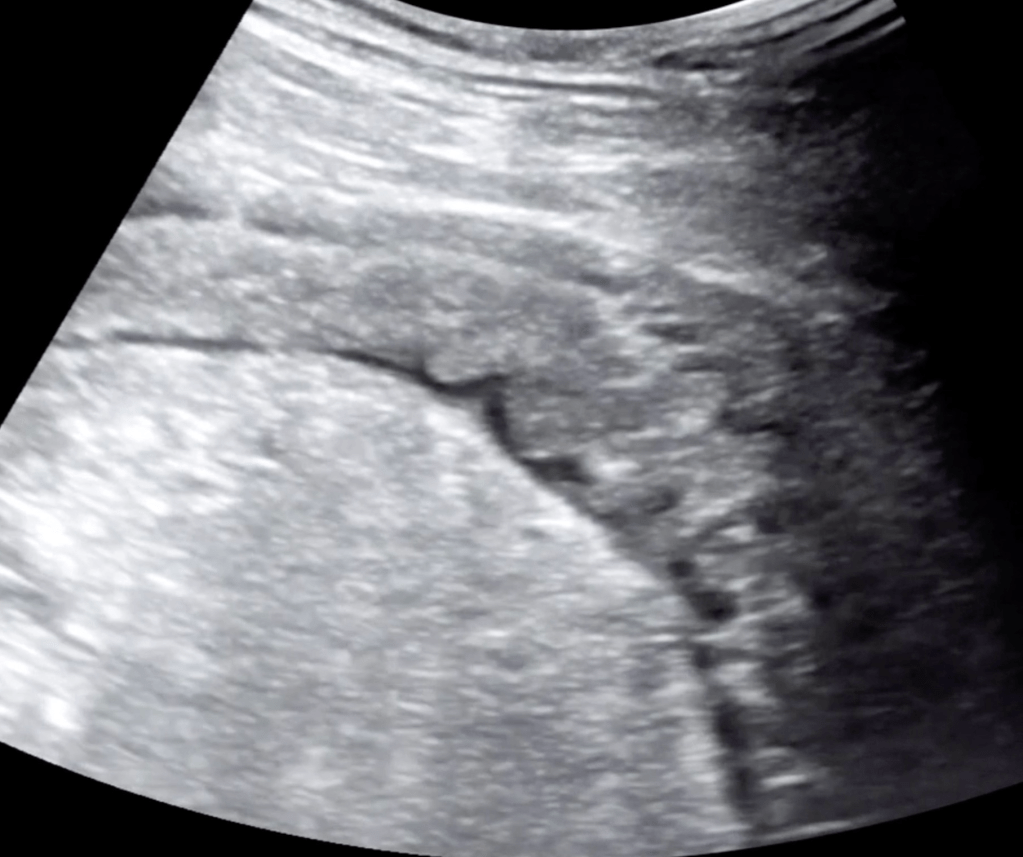

5 Minute Sono

- Large curvilinear probe

- Graded compression up and down

- Diverticula

- Bowel wall>5mm

- Prominent fluid-filled bowel loops

- Pericolic free fluid

- Increased pericolic fat (hyperechoic)

- Abscess